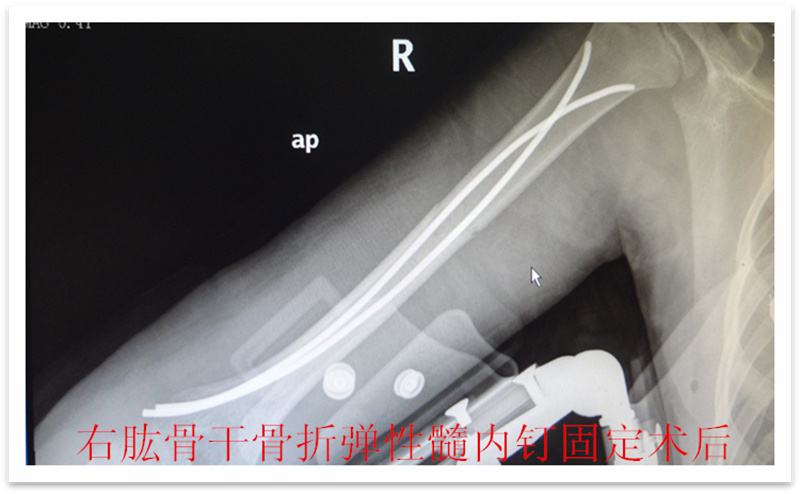

儿童四肢骨折较为常见,保守治疗仍是儿童骨折的重要 治疗方法之一,如牵引,单纯石膏固定等。 往往用时较长,患儿的舒适程度不够,影响患儿及时返回学校学习,这些因素越来越多地影响儿童骨折治疗方法 的选择 。儿童骨折手术治疗的比例较前增加,而传统的手术治疗创伤大,恢复慢,并发症多,如钢板,那是针对成人骨折研发的,用一个坚硬的内固定物固定一个有弹性的骨组织是一个矛盾 ,弹性髓内钉内固定解决了这个矛盾。有人说,弹性髓内钉的出现是上天对儿童的恩惠。的确,弹性髓内钉是治疗小儿长管状骨骨骨折的一种理想、可靠的内固定方法。弹性髓内钉技术发源于法国,在欧洲广泛应用后,现已为全球所接受,被称为是儿童骨科界的一次革命。徐州儿童医院骨一科应用弹性髓内钉技术治疗四肢长管状骨骨折,具有创伤小、恢复快、并发症相对少,孩子能较快恢复正常生活、学习等优点。该技术先将骨折闭合复位,通过微小的切口将特制的弹性髓内钉置入骨髓腔,达到固定骨折的目的。适用于肱骨,股骨,尺桡骨等部位的常见骨折(图)。